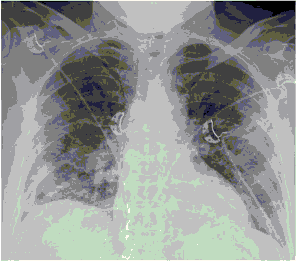

Стандартная РГ имеет низкую чувствительность в выявлении начальных изменений в первые дни заболевания и не может применяться для ранней диагностики. Информативность РГ повышается с увеличением длительности течения пневмонии. Рентгенография с использованием передвижных (палатных) аппаратов является основным методом лучевой диагностики патологии ОГК в отделениях реанимации и интенсивной терапии (ОРИТ). Применение передвижного (палатного) аппарата оправдано и для проведения обычных РГ исследований в рентгеновском кабинете. В стационарных условиях относительным преимуществом РГ в сравнении с КТ являются большая пропускная способность. Метод позволяет уверенно выявлять тяжелые формы пневмоний и отек легких различной природы, которые требуют госпитализации, в том числе направления в ОРИТ.

КТ имеет высокую чувствительность в выявлении изменений в легких, характерных для COVID-19. Применение КТ целесообразно для первичной оценки состояния ОГК у пациентов с тяжелыми прогрессирующими формами заболевания, а также для дифференциальной диагностики выявленных изменений и оценки динамики процесса. КТ позволяет выявить характерные изменения в легких у пациентов с COVID-19 еще до появления положительных лабораторных тестов на инфекцию с помощью МАНК. В то же время, КТ выявляет изменения легких у значительного числа пациентов с бессимптомной и легкой формами заболевания, которым не требуется госпитализация. Результаты КТ в этих случаях не влияют на тактику лечения и прогноз заболевания при наличии лабораторного подтверждения COVID-19. Поэтому массовое применение КТ для скрининга асимптомных и легких форм болезни не рекомендуется.

5. Рекомендовано проведение лучевого исследования пациентам при среднетяжелом, тяжелом и крайне тяжелом течении ОРИ с целью медицинской сортировки, оценки характера изменений в грудной полости и определения прогноза заболевания:

- выполнение КТ легких без внутривенного контрастирования в стационарных условиях или в амбулаторных - при показаниях к госпитализации;

- выполнение РГ легких в двух проекциях, если проведение КТ в данной медицинской организации/клинической ситуации невозможно.